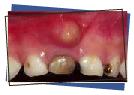

This is a picture of a color change of a tooth associated with a dental abscess. The "pimple" or "bubble" seen above the tooth is an infection (abscess). If you see this in your child's mouth, call our office for an appointment. In most cases, the tooth will have to be extracted. Lack of treatment can lead to more serious problems including damage to the permanent dentition and facial swelling.